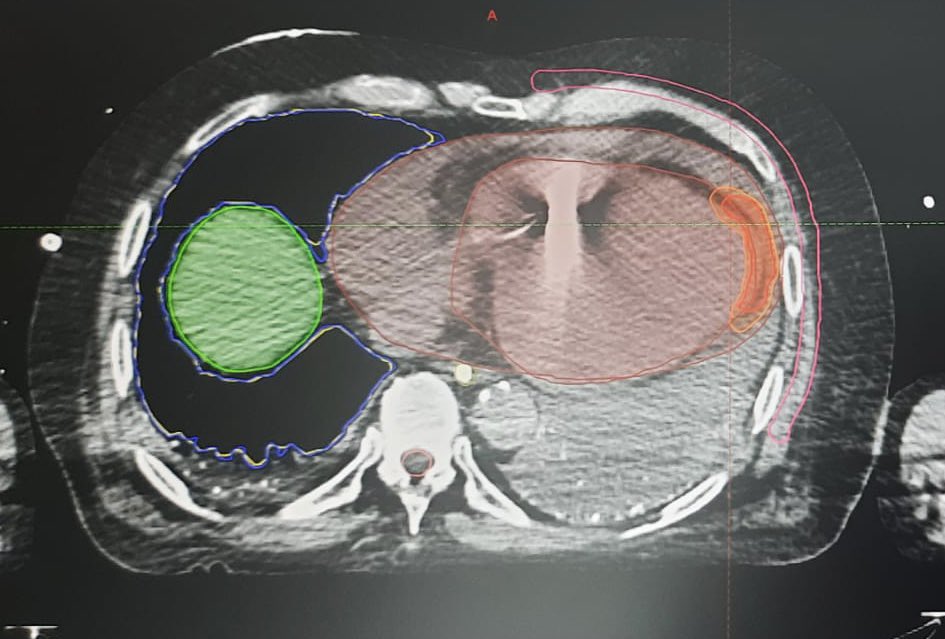

Our first noninvasive VT radioablation case. Who would have ever thought to perform a VT ablation in 6 min. Thanks @DoctorPhillEP for leading the way and @JeffTheEp for the advices. #RadiateVT #EPeeps #AblateVT @SilviaMagnani6